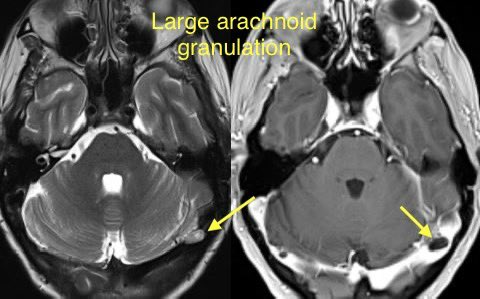

🔷TRANSVERSE SINUS STENOSIS & IDIOPATHIC INTRACRANIAL HYPERTENSION

INTRINSIC: Typically arachnoid granulations

🔹Arachnoid granulations may be incidental though they can produce IIH when obstructing a dominant transverse sinus or simultaneously blocking both

🔹Look for a round/lobulated filling defect with CSF signal on all images